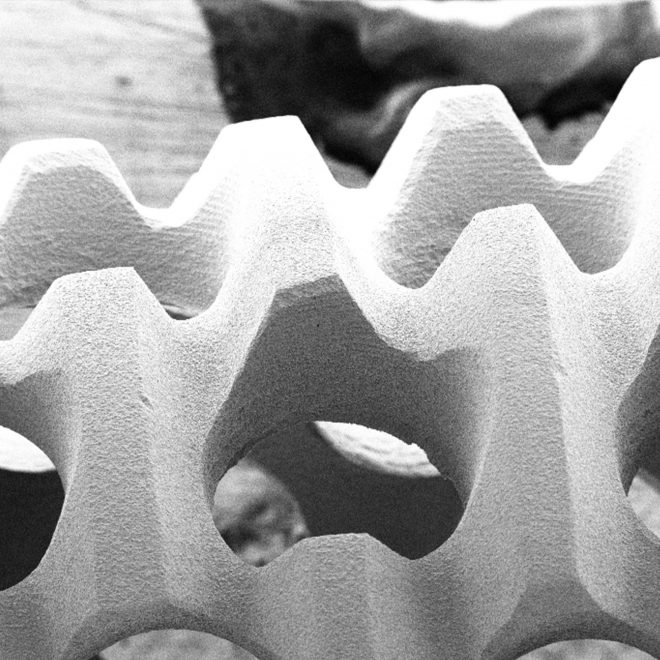

O SUPEX é um tratamento superficial que promove uma área de contato com o osso 100% maior do que os implantes com superfície lisa. Sua superfície rugosa, porém uniforme, é obtida através de um tratamento ácido sequenciado patentead

Esta superfície provê melhores condições de cicatrização e reduz o tempo de osseointegração.

Com esse tratamento conseguimos uma porosidade homogênea [micro e macro porosidade] ideais para a interação entre implante e tecido ósseo.